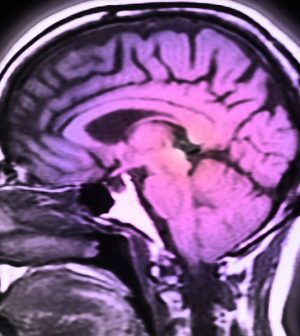

Luckily, most cases are detected early and easily cured via surgery. But sometimes the tumor has had time to spread, even to the brain. In fact, advanced melanomas are now the third-leading cause of metastatic brain cancer, the research team noted.

In its analysis, Iorgulescu’s group tracked outcomes from 2,753 patients with melanoma that had spread to the brain. The patients were treated at cancer centers nationwide between 2010 and 2015.